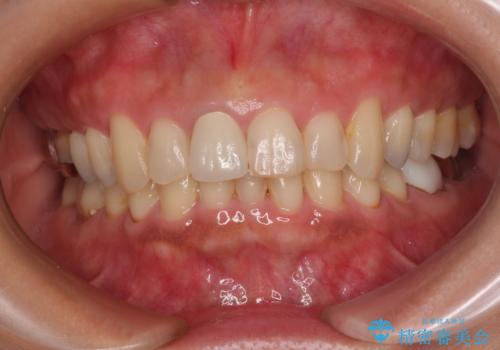

色がやや白いように感じますが、周りの歯をホワイトニングして白くしていくとのことで、明るめの状態での仕上がりとなりました。